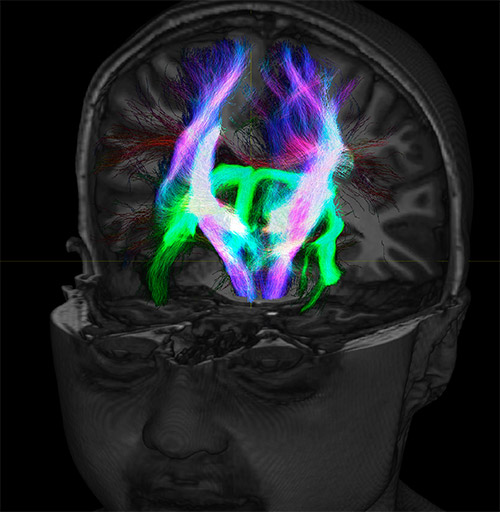

Super-resolution directionally encoded color track-density imaging overlaid on T1-weighted structural MRI.

All images were created from the same acquisition in a child using Ingenia 3.0T CX and 32-channel dS Head coil. Diffusion data was acquired at b-values 0, 500, 1000, 2000, 3000. The use of high b-values (3000 s/mm2) effectively suppresses extra-axonal water signal and provides high angular resolution.